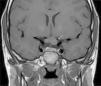

Los GVO suponen el 85% de los gliomas de bajo grado (astrocitomas pilocíticos) de los pacientes con NF1, y afectan al 15-30% de los niños entre 3 y 5 años36,37. Constituyen un criterio diagnóstico de la enfermedad. En la mayoría de los casos son asintomáticos, pero pueden causar pérdida de visión hasta en un 12% de los pacientes37 o pubertad precoz35. La elevada incidencia de los gliomas de nervio óptico hace aconsejable un estrecho seguimiento oftalmológico en los niños con NF1, ya sea clínico o clínico y radiológico, ya que la detección clínica puede ser difícil y algunos neuropediatras prefieren realizar pruebas de imagen complementarias (fig. 6)37. El 15% restante de los gliomas de bajo grado también son más frecuentes en la primera década de la vida, y asientan en cualquier parte del cerebro, manifestándose clínicamente con cefalea, marcha inestable o letargia35. Por el contrario, los gliomas de alto grado (glioblastomas multiformes) son propios de los adultos jóvenes. El riesgo de padecerlos quintuplica el de la población general y tienen mal pronóstico35,38. El tratamiento del GVO en los pacientes con NF1 suele ser conservador, salvo que se observe disminución en la agudeza visual y progresión del tamaño en las pruebas de neuroimagen. En caso de ser necesario, la primera línea de tratamiento es la quimioterapia con vincristina y carboplatino. La radioterapia se desaconseja debido al alto riesgo de tumores secundarios, y el tratamiento quirúrgico queda reservado para tumores orbitales de gran tamaño sin visión útil, con exposición de la córnea o si hay proptosis39.